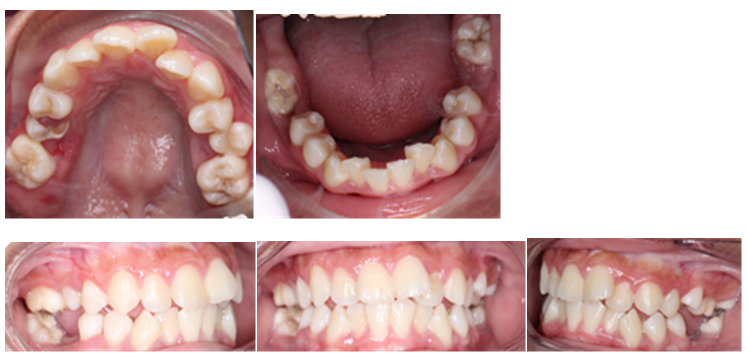

Figure 2. Foto intra oral sebelum perawatan

Pemeriksaan ekstra oral didapatkan profil yang cembung, tipe muka mesosefalik dan bibir tidak kompeten (Gambar.1). Pada pemeriksan intra oral ditemukan berdesakan pada gigi anterior Rahang Atas dan Rahang Bawah. Bentuk lengkung Rahang Atas dan Rahang Bawah adalah normal. Gigi 36 dan 46 tinggal sisa akar. Gigi 12, 22 terletak lebih ke palatal(palatoversi), 21 distolabial rotasi eksentris, 22 palatoversi . Relasi kaninus kanan tonjol dan kaninus kiri neutroklusi sementara molar tidak terdapat relasi. Tumpang gigit dan jarak gigit normal. Terdapat pergeseran garis median Rahang Atas 1 mm ke arah kiri. Analisis model menunjukan terdapat diskrepansi berupa kekurangan tempat 8 mm di Rahang Atas dan Rahang Bawah terdapat kekurangan tempat sebesar 4 mm (Gambar.2)